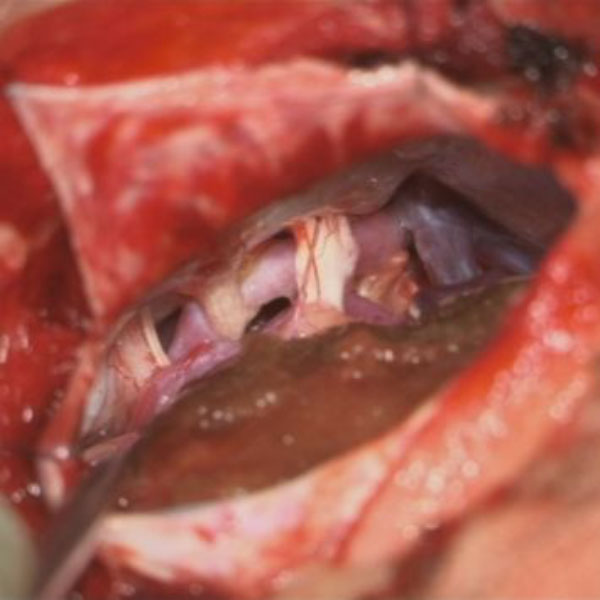

手術中

処置前

処置後